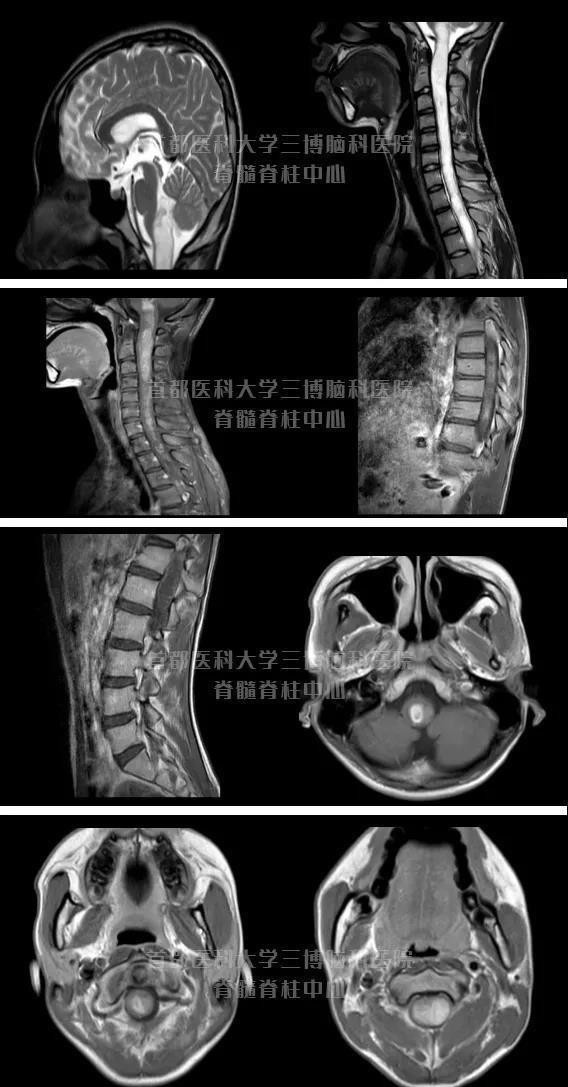

今年年初正在备考中考的他,总是莫名地出现头痛,吃饭也吃不了多少,还容易吐。他本想坚持中考完后,和妈妈一起去医院看看。没想到在中考前几天,病情一直在加重,上课经常趴着,左上肢越来越没有力气,还出现了肌肉的萎缩的症状。家人一看情况不妙,就急送到当地医院,行头颈核磁检查,发现自延髓向下广泛髓内占位性病变,下界不明确。当地大夫当即建议直接去北京看病吧。小王是家里的独子,母子俩相依为命,得知他长了一个危险的大肿瘤,他们陷入了恐慌和无助中。那一刻,虽是大热天,但母子俩感觉特别冷,冷到骨子里。家庭生活困顿 妈妈曾要求三次出院在多方打听下, 小王和妈妈秦女士找到首都医科大学脊髓脊柱外科范涛教授,他的团队范涛已开展各种脊髓脊柱外科手术5000台,曾完成3mm脊髓内肿瘤和300mm脊髓内肿瘤全切除手术。入院时,小王是背着进来的,路都走不了。范涛教授给小王安排了全面的检查。不看不知道,一查吓一跳。脊柱核磁成像提示延髓至脊髓圆锥全长髓内脊髓肿瘤,伴脊柱侧弯畸形颈椎侧凸,胸段侧弯45度。“这个孩子的脊髓有多长,这个肿瘤就多长,只有一个到两个椎体的阶段是有一部分空洞,其他部分全是实性肿瘤”范涛教授介绍。

全脊柱核磁可见延髓至脊髓圆锥髓内占位,伴随脊髓空洞